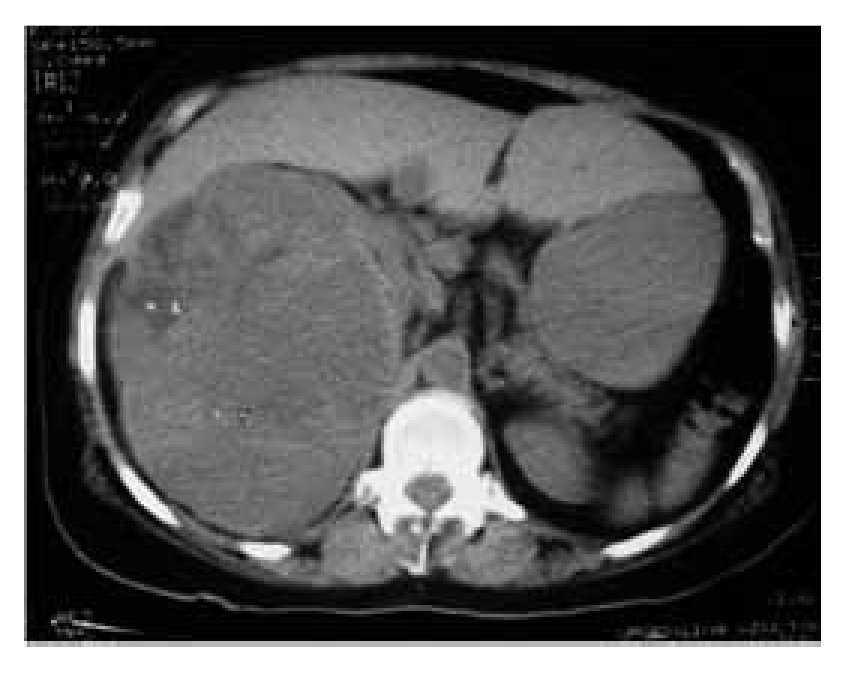

Paciente femenina de 71 años de edad, padre diabético, madre hipertensa. Acudió por masa dolorosa en flanco derecho, de 2 meses de evolución, asociada a pérdida de peso de 7 kg y escalofrío eventual. A la exploración física con presión arterial de 120/80 mmHg, tórax normal, abdomen blando, depresible, masa dura, dolorosa, que involucra todo el hemiabdomen derecho. Exámenes de laboratorio con Hb: 10.7, creatinina: 1.22, examen general de orina: 3-4 eritrocitos por campo, pruebas de funcionamiento hepático normales, radiografía de tórax normal, tomografía computadorizada y angiorresonancia: masa sólida heterogénea, con áreas de necrosis y con escasa captación de contraste, sin afección de grandes vasos (Imágenes 3 y 4). Se efectuó nefrectomía radical, tumor con dimensiones de 27 x 15 x 18 cm dependiente de polo inferior (Imagen 5).

Imagen 3. Tomografía computadorizada a los dos meses de evolución, en la que se identifica una masa sólida heterogénea.

Imagen 4. Angiorresonancia: masa sólida heterogénea, con áreas de necrosis y con escasa captación de contraste, sin afección de grandes vasos con áreas de necrosis y con escasa captación de contraste, sin afección de grandes vasos.